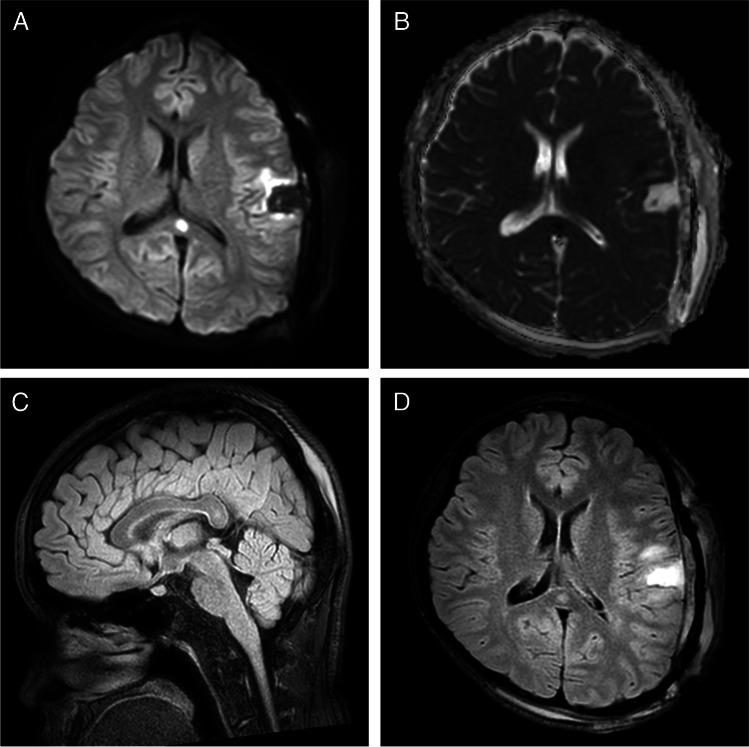

Isolated lesions of the corpus callosum are rare and may represent permanent but also transient responses to various pathology termed "reversible splenial lesion syndrome" (RESLES) when in light of relevant clinical presentation. We present the first case of the RESLES after elective surgery for distant arteriovenous malformation (AVM), followed by a slight speech disturbance and MRI verified small, oval, well-circumscribed area of apparent cytotoxic edema in the center of the corpus callosum splenium, which completely resolved within 15 days. Surgery for AVM is followed by the complex adaptation to a new vascular pattern, RESLES might develop, and should be suspected.

孤立性胼胝体病变较为罕见,在结合相关临床表现时,可能代表对各种病变的永久性或一过性反应,这种病变被称为“可逆性胼胝体压部病变综合征”(RESLES)。我们报告首例 RESLES 病例,患者因远处动静脉畸形(AVM)选择性手术,随后出现轻微言语障碍,磁共振成像(MRI)证实胼胝体压部中心存在小的椭圆形、边界清楚的明显细胞毒性水肿区,15 天内完全消退。AVM 手术后需要进行复杂的血管模式适应,RESLES 可能会发展,因此应怀疑该综合征。